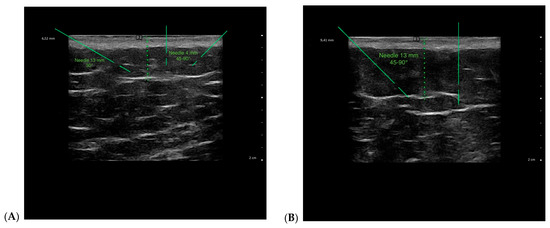

Background: Cellulite is a highly prevalent aesthetic concern characterized by structural remodeling of subcutaneous adipose tissue and fibrous septa, resulting in visible skin irregularities. Despite the availability of many injectable treatments with documented efficacy, most standard approaches adopt uniform protocols that overlook interindividual anatomical variability, potentially limiting treatment precision and clinical outcomes. This retrospective case–control study evaluated the Modulated Insertion of Regenerative Activation (MIRA), a technique that individualizes needle length and injection angle according to ultrasound findings, modulating insertion parameters to stimulate regenerative responses within dermal and subcutaneous layers. Methods: Clinical and ultrasonographic data from 120 women with stage 3 cellulite were analyzed over a 30-day follow-up period. Stage 3A patients received carbon dioxide therapy (CDT), whereas stage 3B patients underwent injectable solution therapy (IST). Within each treatment, patients were allocated to MIRA or control groups. Results: Compared with controls, MIRA showed greater reductions in adipose tissue thickness (CDT: −1.6 mm; IST: −1.5 mm; padj = 0.002), nodules, pain, edema, and fibrosis, with improved fascia regularity. Patient satisfaction was higher in MIRA (CDT: 8.1 ± 1.6; IST: 8.5 ± 1.4; padj = 0.002), and over 76% reported improved skin quality. Conclusions: These explorative findings suggest that ultrasound-guided modulation of needle parameters with MIRA may enhance structural and esthetic outcomes compared with standard approaches. Prospective randomized trials are needed to confirm these results. Full article

Show Figures

Figure 1